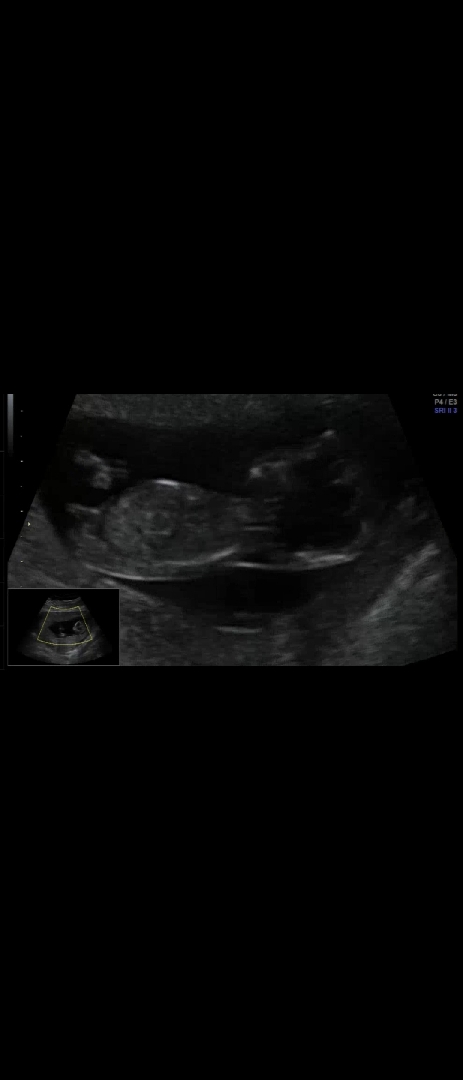

성별투표 찍어주세욧 !

두근두근